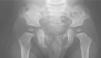

Exploraciones complementariasSe efectuó una ecografía renal y una analítica de sangre y orina que no mostraron alteraciones, un examen oftalmológico que tampoco evidenció patología y, por último, se realizó una serie ósea de la columna, las extremidades, las crestas ilíacas y las caderas en la cual se pudo apreciar la presencia de cuernos ilíacos posteriores (fig. 3).

ComentariosEl síndrome uña-patela es un trastorno raro, de herencia autosómica dominante con penetrancia y expresividad variables. Se caracteriza por 4 signos mayores que consisten en: uñas displásicas con lúnula triangular, rótula hipoplásica o ausente, cuernos ilíacos posteriores y cabezas radiales hipoplásicas. No todos ellos están presentes en todos los casos. Otras alteraciones posibles incluyen: afectación ocular y renal, aneurismas arteriales, retraso psicomotor o crisis convulsivas. La afectación ungueal ocurre en un 98 % de los casos. Las uñas displásicas están presentes al nacimiento1. Típicamente se ven afectadas de forma más intensa las uñas de los tres primeros dedos de las manos, mostrando alteraciones como hipoplasia, ausencia, morfología en cuchara o estriación longitudinal. La presencia de lúnulas triangulares es un hallazgo característico. Además, puede asociarse a una hipoplasia de las falanges distales2. La hiponiquia y la anoniquia congénitas son malformaciones raras que pueden formar parte de síndromes como el uña-patela, las displasias ectodérmicas y las braquidactilias, o pueden ocurrir como un hallazgo aislado. Estas alteraciones se asocian con frecuencia a una afectación esquelética subyacente3. Entre los hallazgos óseos destacan los cuernos ilíacos posteriores, generalmente bilaterales y presentes hasta en un 80 % de los casos4, y la displasia de codo y rótula (en más de un 90 %), lo que origina subluxaciones y artrosis precoz. También puede estar presente una hipoplasia de las escápulas 2. Hay que tener en cuenta que la rótula no se osifica por completo hasta la infancia tardía, por lo que se debería realizar una ecografía según la edad del paciente para poder valorar la misma. En un 25-50 % de los casos se asocia a nefropatía, que es la principal complicación por la posibilidad de fallo renal hasta en un 10 % de los casos. La alteración se presenta fundamentalmente como proteinuria asintomática o glomerulonefritis, apareciendo en el sedimento hematuria, albuminuria y cilindros hialinos1,5.